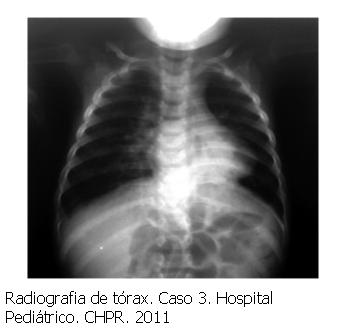

Caso 3. 13 meses, sexo masculino, peso 5.260 g. Síndrome de Down, comunicación interventricular e interauricular sin repercusión hemodinámica, ingresa por desnutrición crónica para reparación nutricional. A los 40 días de hospitalización bronquiolitis con insuficiencia respiratoria (figura 4), antígenos virales negativos. Se inicia tratamiento con escasa respuesta, mantiene escore de Tal 7, frecuencia respiratoria 66 rpm. Gasometría arterial pH 7,35 PCO2 36 mmHg HCO3 22 mEq/L BE: -3 Se inicia OAF. Mejoría clínica a las 2 horas, frecuencia respiratoria 44 rpm, escore de Tal de 5, gasometría arterial pH 7,39 PCO2 43 mmHg PO2 110 mmHg BE: 1 y Sat O2 99%. Permanece en OAF 72 horas, posteriormente oxigenoterapia con cánula nasal a 1 l/min.